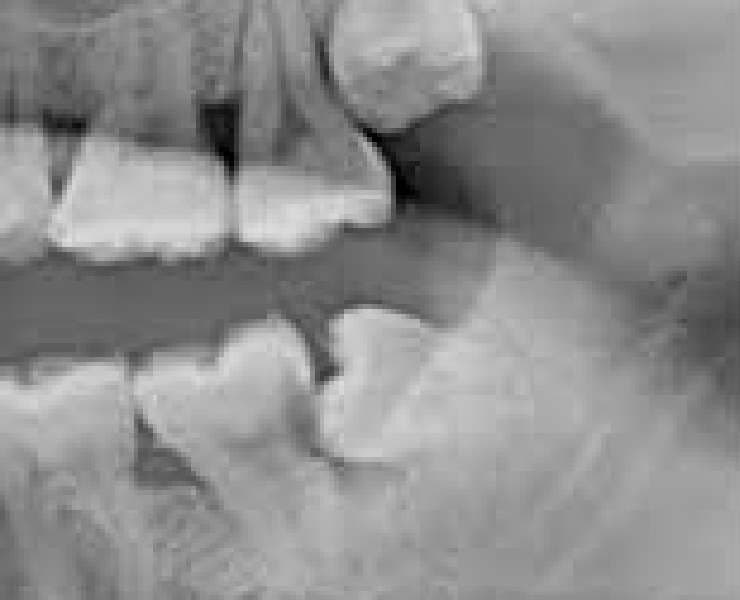

親知らずが原因で手前の歯がむし歯になった症例

親知らずと手前の歯の間に黒い影があります。

この黒い影がむし歯です。むし歯が横から進行していくと、神経の処置が必要となる可能性が高まります。